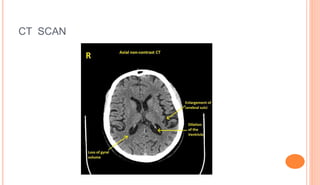

CT SCAN